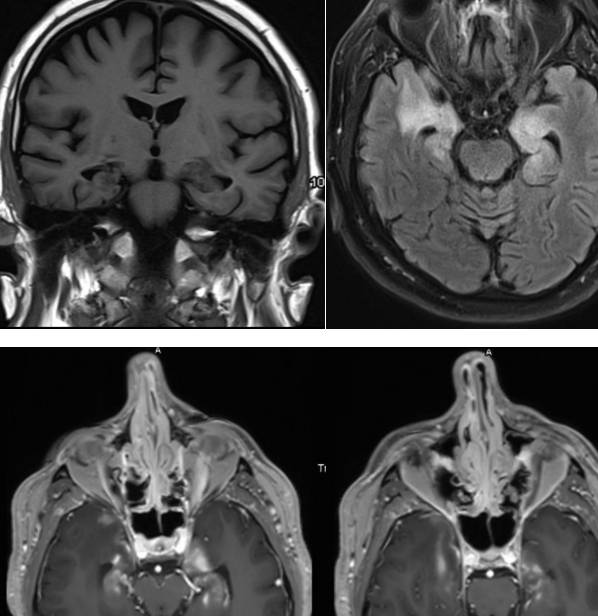

26岁,女,右侧肢体无力伴意识模糊1月余。既往史:月经周期不规则,两年前停经。1年前体重增加18公斤,伴双手、脚踝对称性肿胀,面部浮肿。3月前出现多尿、多饮,空腹血糖升高,每天尿液超过10升。既往无烟酒、毒品接触史。查体:体重指数34.6,皮肤、口腔粘膜、甲床苍白。皮肤干冷,双侧手、脚踝水肿,阴毛稀疏。神经查体:昏睡,表达性失语症。右侧周围性面瘫,右上肢完全瘫痪,右下肢部分瘫痪。左侧肌力正常。右侧腱反射消失,左侧腱反射正常。右侧病理征阳性,左侧病理征阴性。无感觉异常。辅查:贫血,高钠血症伴低渗性多尿。血糖高,甲减,性激素示FSH、LH、PRL降低。ESR、CRP升高,狼疮、干燥等风湿抗体阴性。

脑寄生虫病、低灌注脑梗死、基底动脉尖综合征丨3分钟读片 ...

答案:朗格汉斯细胞组织细胞增生症。朗格汉斯细胞组织细胞增生症是一组少见的瘤样病变,发生在骨组织的反应性、非肿瘤性、增生性疾病。多见于20岁以下青少年。其临床表现:骨骼病损、皮肤黏膜损害、淋巴结损害、肝脏及脾脏损害、肺脏损害、女性生殖系统损害、内分泌系统损害、其他表现(长期发热、胃肠道受累、中枢神经系统受累等)。影像:1)中枢神经系统:矢状位可发现垂体后叶T1WI高信号消失。部分病人可见垂体柄增粗或下丘脑孤立性强化结节。2)呼吸系统:胸部CT:双肺多发结节并弥漫分布大小不一囊性病变,中上肺野为著,囊壁厚薄不规则。4、活检:1)光镜:朗格汉斯细胞灶状或片状排列是本病的特征;2)电镜:朗格汉斯细胞中特有的Birbeck颗粒;3)免疫组化:S2100蛋白阳性、CD1a(冷冻切片)或MAb010(石蜡切片)阳性为其特征。